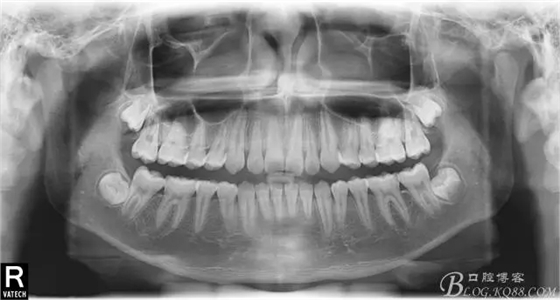

術后全景,側位照。